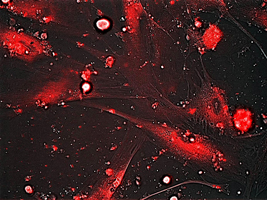

Imagen: Liberación controlada de la molécula fluorescente rodamina en

fibroblastos senescentes de pacientes con disqueratosis congenita,

mediante el nanodispositivo.

Los investigadores han evaluado la utilidad de los nuevos

nanodispositivos en cultivos celulares primarios derivados de pacientes

con el síndrome de envejecimiento acelerado Disqueratosis Congénita.

Dichos cultivos presentan un alto porcentaje de senescencia,

caracterizada por elevados niveles de actividad de betagalactosidasa,

una enzima característica del estado senescente. “Las células

envejecidas sobreexpresan esta enzima; las nanopartículas que hemos

diseñado se abren ante su presencia, liberando su contenido para

eliminar las células senescentes, prevenir su deterioro o incluso

reactivarlas para su rejuvenecimiento”, explica Murguía.